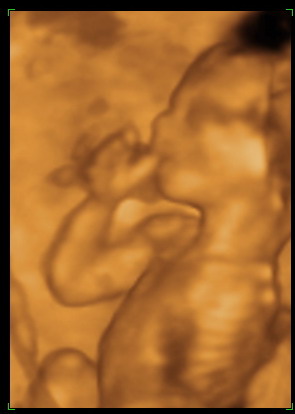

Na még pár képpel bombáznék, íme Zsebihal: :)

[img][img]https://www.babanet.hu/tarsalgo/attachments/1214857782.3077.jpg[/img]

[/img] Kép

[img][img]https://www.babanet.hu/tarsalgo/attachments/1214857829.1758.jpg[/img]

Kép

Mágnes: nagyon szuperek a képek..és hogy látszik a kezecskéje ahogy a szájánál van,,:Dcumizza? mert ugy néz ki. áááá..el vagyok ájulva..

Ejj, ez a Zsebike, napról-napra édesebb! :)

Na, visszajön a néni, UH fej fel a pocira, és mit látunk: teljesen megfordult a kis tökös! :lol:

Aztán jött az ujjszopi:

Kép .

később meg a lábfelpakolás, merthogy csak kényelmesen ám! :lol:

Szóval, produkcijjjó az volt rendesen! :lol: :lol: :lol: :lol:

Bizony az ujját szopta, tiszta nővére :) Doki bácsi szerint festett.

Nagyon édes tökitek van :) Ő is ujjszopis :wink:

Mágnes: szerintem csak azért produkálta magát most ennyire, mert korábban még mocorogni sem volt hajlandó az UH-kon, gondolta, nah, most hadd olvadozzanak az ősök... :P :P

Mágnes, Bébic! Gratula az ujjszopisokhoz! Nagyon drágák!